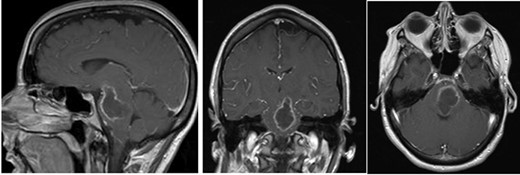

She presented to clinic for follow-up evaluation 11 weeks after discharge. Overall, she is doing very well and ambulating independently with a cane. On physical exam, CNII-XII are intact. She has no bulbar deficits. She has 4/5 strength in all major muscle groups on the right side. Repeat MRI has shown near resolution of the abscess (Fig. 3a and b).

Post-op axial and coronal MRIs, 11 weeks following discharge, demonstrating resolution of the pontine abscess with small area of residual scarring; source: http://pacsweb.wjmc.org.